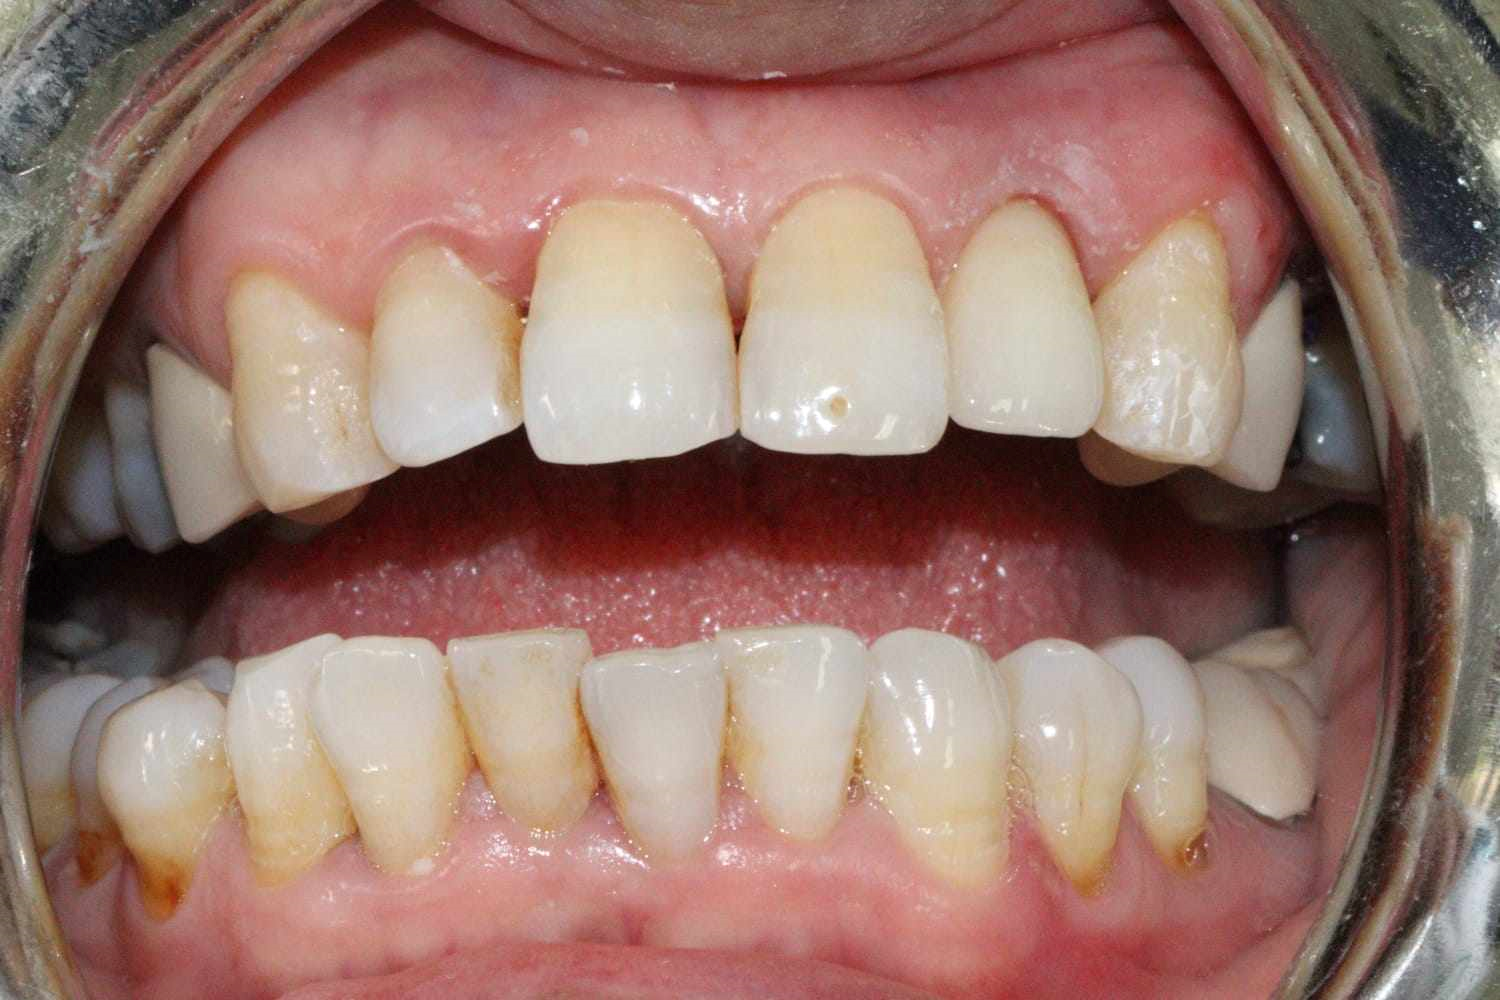

Radiological examination (Figure 2) showed no periapical infection or desmodontal enlargement, and the presence of a thin layer of vestibular bone, so tooth 22 was deemed irrecoverable.

Figure 2. Sagittal sections of the CBCT of the patient